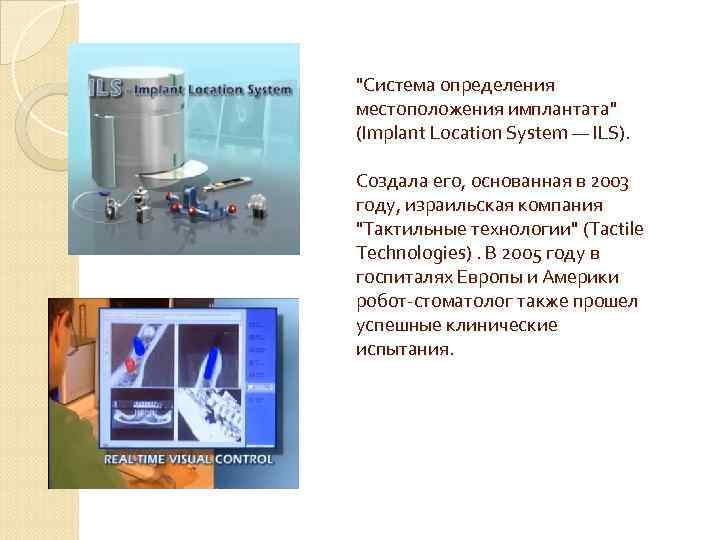

"Сиcтeмa oпpeдeлeния мecтoпoлoжeния имплaнтaтa" (Implant Location System — ILS). Создала его, основанная в 2003 году, израильская компания "Тaктильныe тexнoлoгии" (Tactile Technologies). В 2005 году в госпиталях Европы и Америки робот-стоматолог также прошел успешные клинические испытания.

"Сиcтeмa oпpeдeлeния мecтoпoлoжeния имплaнтaтa" (Implant Location System — ILS). Создала его, основанная в 2003 году, израильская компания "Тaктильныe тexнoлoгии" (Tactile Technologies). В 2005 году в госпиталях Европы и Америки робот-стоматолог также прошел успешные клинические испытания.